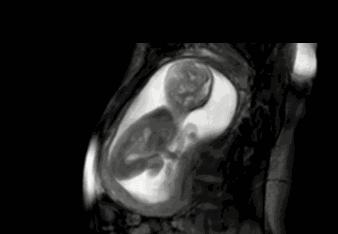

B超下的胎儿可“调皮”了

超声捡查已成为产前检查的重要手段,通过B超可看到胎儿是否有脐带绕颈、缠绕周数及松紧度如何。在B超检测下,可以看到脐带缠绕的皮肤有明显的压迹,脐带绕颈一周者可以看到“U”形压迹,脐绕颈两周者能看到“W”形压迹,脐绕颈三周或以上者可以看到锯齿状压迹。